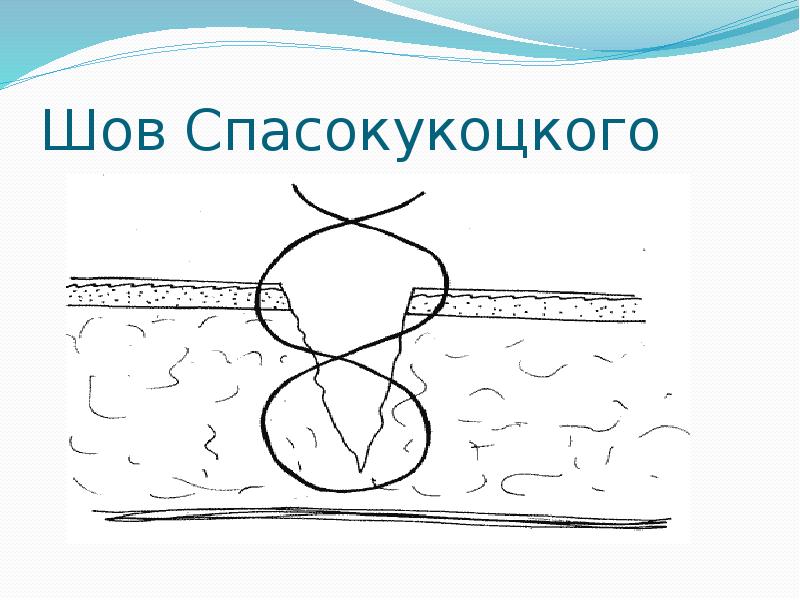

- 37. Кожный шов М.Б. Замощина